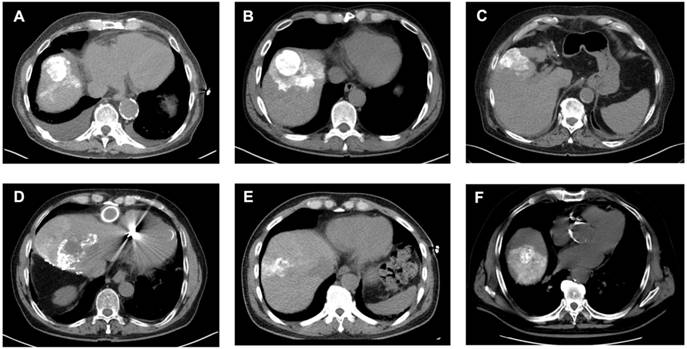

Figure 4

Analysis of Lipiodol Deposition and Distribution Patterns post-cTACE. Legend: CT scans obtained 24 hours after cTACE show different patterns of Lipiodol deposition within target tumors. Homogeneous deposition (A-C) was defined as ≥85% of the tumor volume containing medium or high-density Lipiodol. Heterogeneous deposition (D-F) was defined as <85% intratumoral Lipiodol uptake, characterized by patchy, irregular, or incomplete filling of the tumor. Lipiodol distribution was classified as confined to the tumor, without visible extension into the surrounding liver parenchyma (i.e., A), extending into one adjacent liver segment, without extension into additional segments (i.e., B, E, F), or extending beyond the tumor-bearing segment into at least one adjacent liver segment (i.e., D).

However, when patients were stratified according to Lipiodol distribution, baseline serum IL-6 was significantly elevated in patients with tumoral compared to the segmental Lipiodol distribution (3.75 ± 0.73 pg/mL vs. 2.37 ± 0.65 pg/mL, p = 0.0033). In post-cTACE serum, IL-10, IL-4, TNF-α, and IL-5 were significantly higher in the tumoral group compared to the “segmental” group (IL-10: 2.1 ± 1.07 pg/mL vs. 0.41 ± 0.07 pg/mL, p = 0.0006; IL-4: 0.016 ± 0.003 pg/mL vs. 0.008 ± 0.004 pg/mL, p = 0.0018; TNF-α: 1.93 ± 0.28 pg/mL vs. 1.27 ± 0.13 pg/mL, p = 0.0197; IL-5: 0.97 ± 0.64 pg/mL vs. 0.24 ± 0.06 pg/mL, p = 0.0375). Post-cTACE TIF cytokine analysis revealed no statistically significant differences between patients with tumoral and segmental Lipiodol distribution, respectively. Full data is provided in Supplementary Table S11. Representative imaging examples illustrating Lipiodol deposition and distribution patterns are shown in Figure 4. The associations between Lipiodol deposition and distribution patterns and post-cTACE serum cytokine levels are summarized in Figure 5.

In the cTACE/iBT group, Lipiodol distribution was assessed on non-contrast-enhanced CT acquired 24 h post-cTACE. Assessment focused on (a) the homogeneity of intratumoral Lipiodol deposition and (b) the distribution between target and non-target regions. Lipiodol deposition (a) was classified as homogeneous if ≥ 85% of the tumor volume demonstrated medium-to-high attenuation, and as heterogeneous if < 85% of the tumor was covered or if only low attenuation was observed. Lipiodol distribution (b) was further categorized as tumor-only (confined to the tumor) or segmental (extending into adjacent liver segments). Segmental deposition was further subdivided into single segment or multiple segments, depending on the extent of spread [37-39]. Image analysis was performed by two readers with 3 and 10 years of experience in abdominal imaging based on consensus. Detailed MR and CT imaging protocols, signal intensity measurements, and region of interest (ROI) analysis are described in the Supplementary Methods.